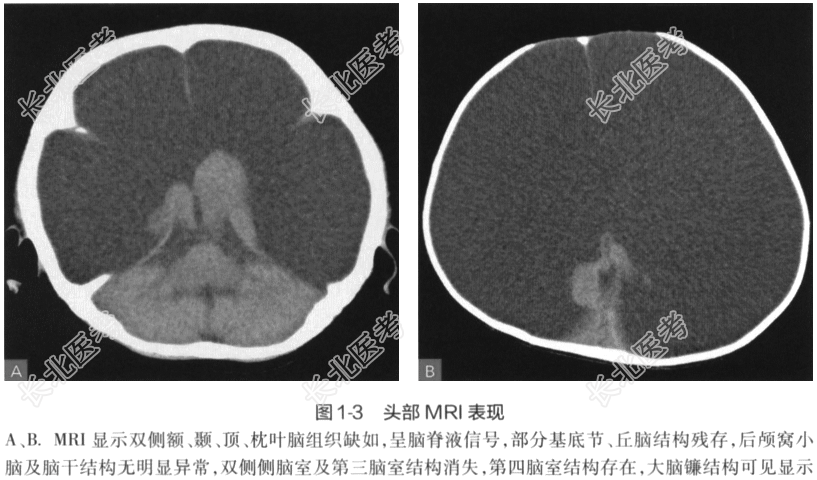

- [材料题] 患者,玄性,5个月。头围渐进性增大,精神、运动发育迟缓,烦躁、易激惹,间断性抽搐发作。查体见前囟增大、膨隆,肌张力增高,吸吮反射减低,颅骨透光试验阳性。影像学检查: